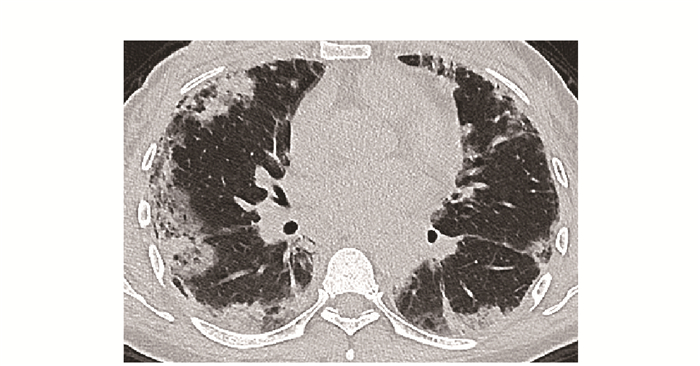

• 摘要: 结缔组织病累及呼吸系统可表现为间质性肺疾病、弥漫性肺泡损伤、肺泡出血、肺血管病变、胸膜病变及气道病变等。其临床表现缺乏特异性, 肺功能和胸部CT是最常用的检查手段。不同结缔组织病累及呼吸系统的影像特征具有相似性, 但又各具特点。本文就结缔组织病呼吸系统受累相关影像表现进行概述, 以提升读者的认知并指导临床实践。

Abstract: Respiratory manifestations of connective tissue diseases include interstitial lung diseases, diffuse alveolar injury, alveolar hemorrhage, pulmonary vascular lesions, pleural lesions and airway disease. Their clinical symptoms were not specific. Pulmonary function test and chest computed tomography come to be the most frequently applied examinations. Different connective tissue diseases involving respiratory system have not only common features but also characteristic imaging patterns. In this paper, imaging manifestations of respiratory diseases associated with connective tissue diseases were reviewed, so as to improve readers' recognition of the diseases and guide clinical practice.